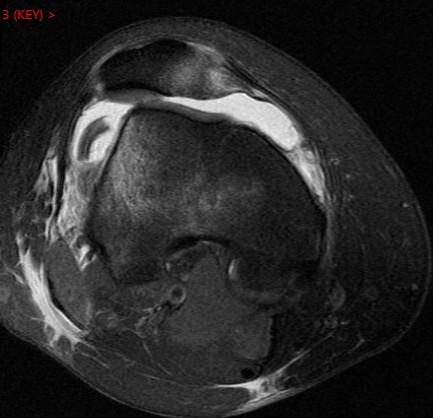

Figure 3 for case Patellar dislocation

Figure 3

Discussion

All the classic findings. Im showing this one because of the loose chondral body knocked off of the patella. Nice example.

Patellar dislocation